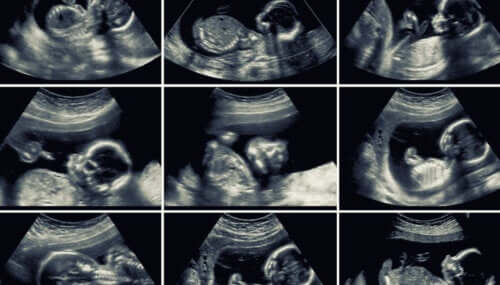

L’échographie de 20 semaines est un examen de routine qui permet une évaluation approfondie des organes du bébé, de l’utérus de la mère et du placenta. En plus des informations précieuses qu’il offre, il est réalisé à un moment clé de la grossesse.

Lorsque vous arrivez au milieu de la grossesse, l’obstétricien demande généralement une échographie morphologique qui, comme son nom l’indique, vise à analyser l’anatomie du bébé.

Cet examen s’effectue entre les semaines 18 et 20 de gestation pour un certain nombre de raisons qui favorisent la visualisation fœtale:

- La quantité de liquide amniotique est suffisante pour obtenir des images claires.

- Le bébé a acquis juste la bonne taille pour examiner ses structures et aussi pour voir tout son corps à la fois.

- Les organes fœtaux sont presque entièrement formés. Leur morphologie et leur emplacement peuvent être analysés en profondeur.

En général, cette échographie se fait en 2D. Cependant, si l’appareil le permet, certaines images peuvent être capturées en 3D ou 4D. Ces derniers montrent avec plus de précision les traits du visage du bébé et même ses mouvements en temps réel.

Le spécialiste peut combiner des images 2D et 3D pour une analyse plus complète de toutes les structures du bébé.